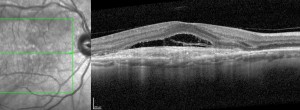

Ensayo clínico TALON: Eficacia y seguridad de brolacizumab en el tratamiento de la DMAE exudativa